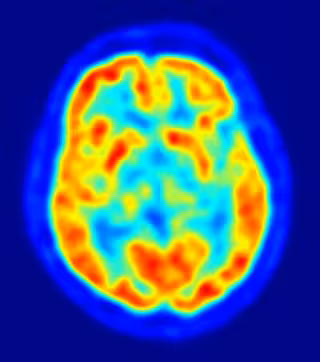

cerebro, recurso, neuronas

JENS LANGNER